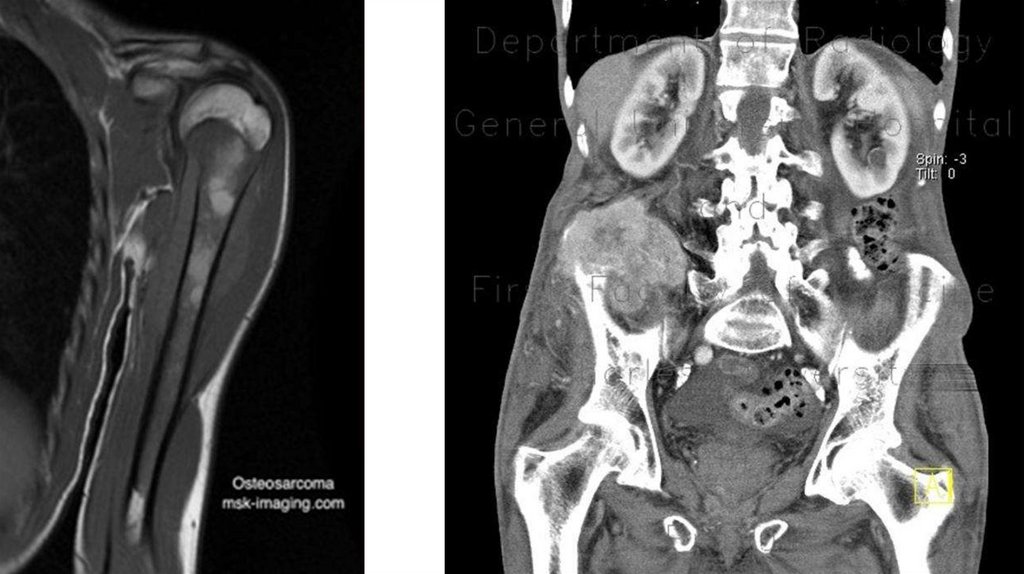

Диагностика

• Рентгенография (очаг деструкции, игольчатый периостит,

«козырек» Кодмана)

• КТ

• МРТ с контрастированием

• Сцинтиграфия с технецием

• Биопсия (высокий полиморфизм с наличием большого количества

митозов, наличие новообразованных остеоидных структур)

• Поиск метастазов